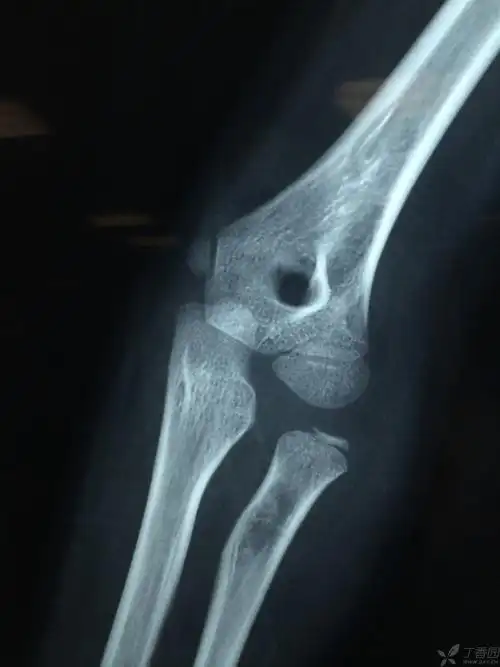

桡骨小头脱位,请求治疗方案 - 骨科 - 专业医生社区,医学,药学,生命